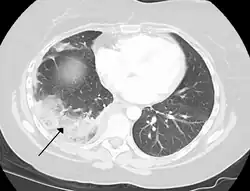

- Chest CT (axial lung window)